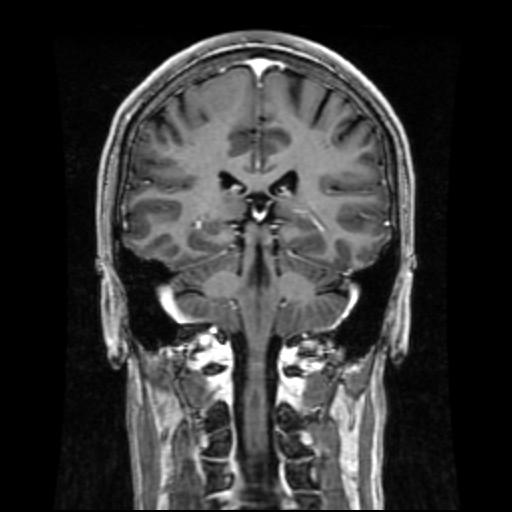

what view is this?

coronal

which plane is shown here?